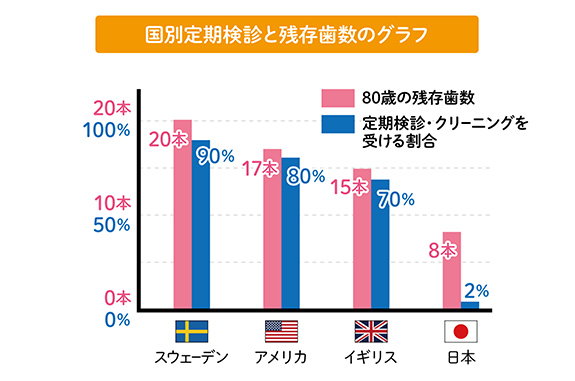

自分の歯で噛める80代を

目指して!

日本では定期検診へ通う習慣がある方はまだまだ少数です。しかしそれは80歳時の歯の残存本数に大きな差となって表れてきます。未来の歯の健康を考えるなら、定期検診をライフスタイルに組み込むことはとても重要だといえます。